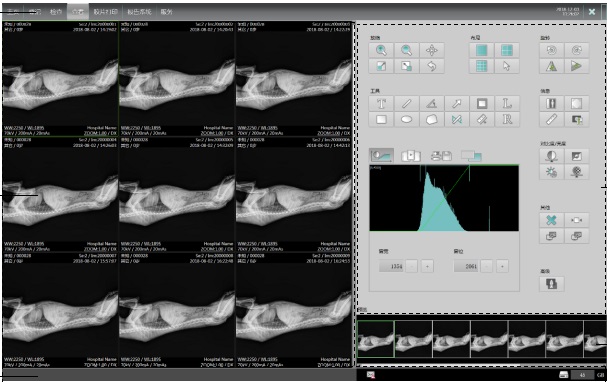

圖像后處理技術:必須符合獸醫術語與操作規范,具有自動影像增強清晰技術,以減少因動物移動造成的偽影,避免誤診和漏診。

系統設置:選擇操作簡便、自動化程度高的設備,具有一鍵優化處理功能,便于醫生使用,提高設備效率。

四、熟悉軟件工作站的性能

自主研發能力:首選有自主研發能力的品牌,確保軟件系統的穩定性和更新能力。

符合國際標準:軟件工作站應符合DICOM3.0國際標準,可連接PACS系統,具備先進的圖像處理能力。

智能AI曝光系統:操作簡單,劑量安全,提升診斷效率。